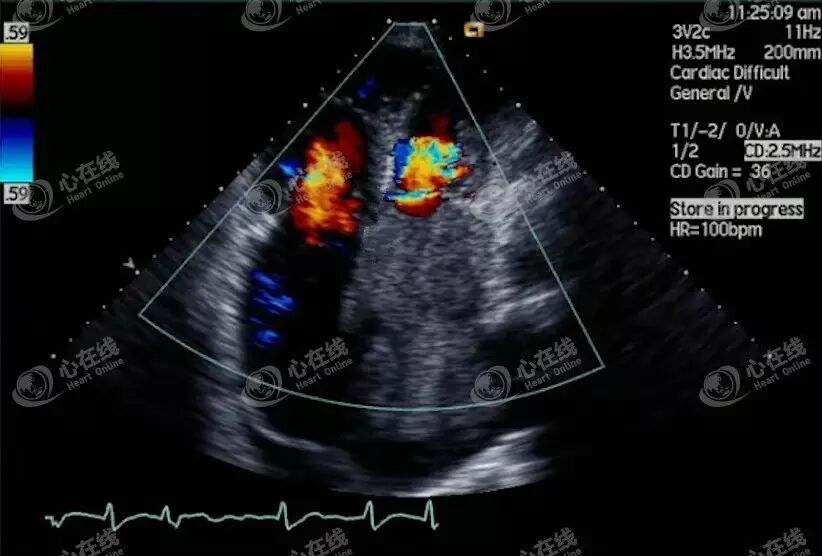

观察上图可见二尖瓣口高速血流、三尖瓣血流,且瓣膜存在反流,左房内有浓密的“雾影状”回声,提示风湿性瓣膜病。